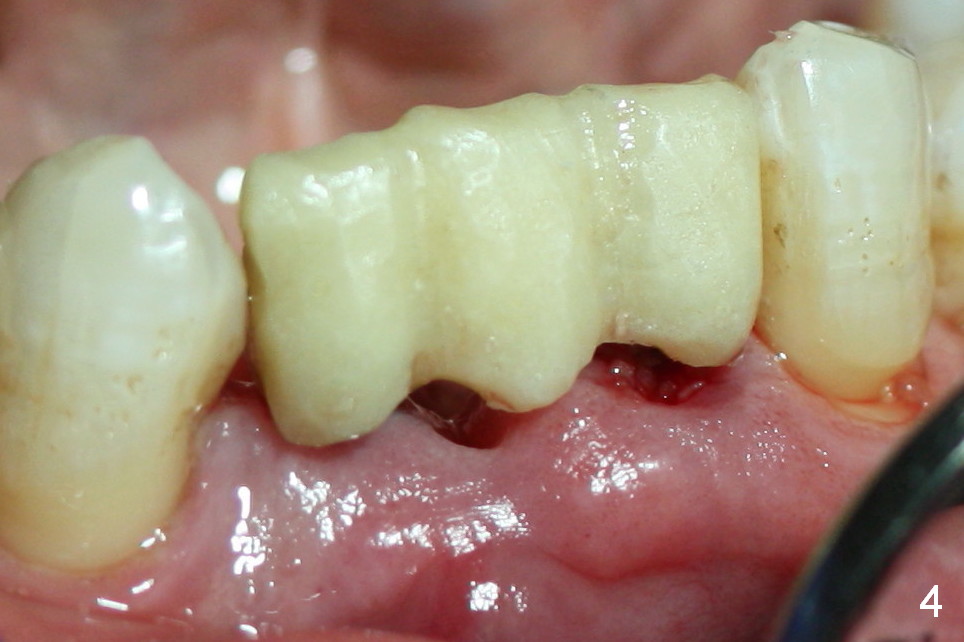

One of the functions of an immediate provisional is to maintain and create the valleys and peaks of the gingival morphology (Fig.4-6). When the wound heals initially, the provisional should be modified (Fig.5 yellow curves) to push the gingiva aside (Fig.6 arrows) to create oval pontic and papillae (Fig.5).